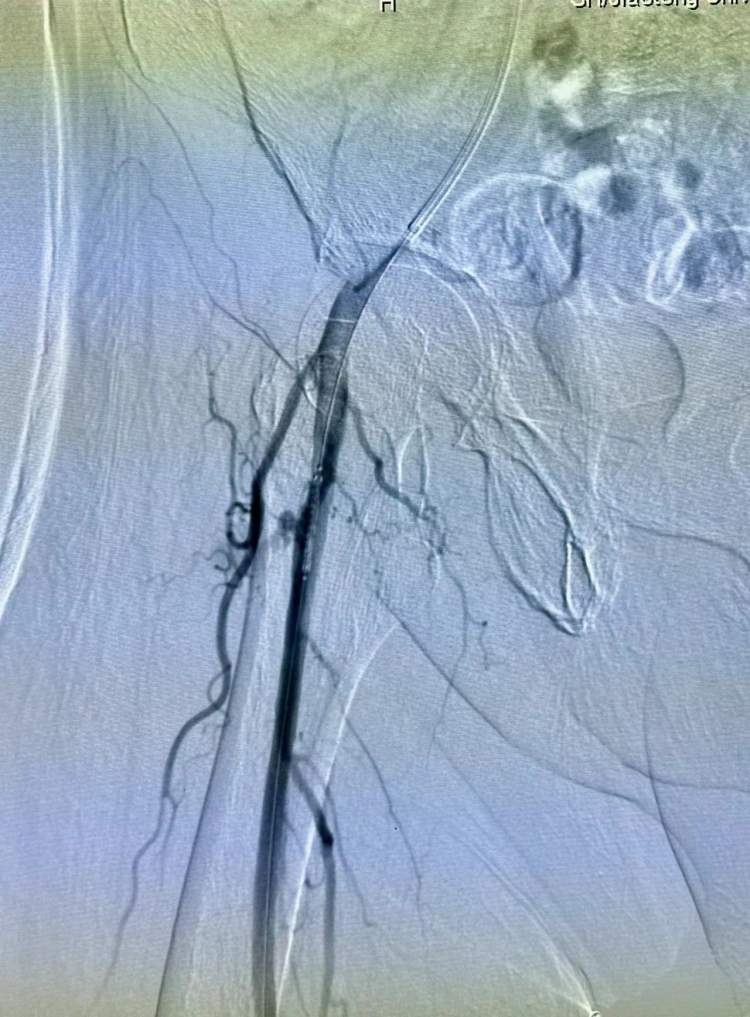

手术正常进行。王忠敏主任刚手术完,接受手术的是右侧股动脉假性动脉瘤,大出血病人。